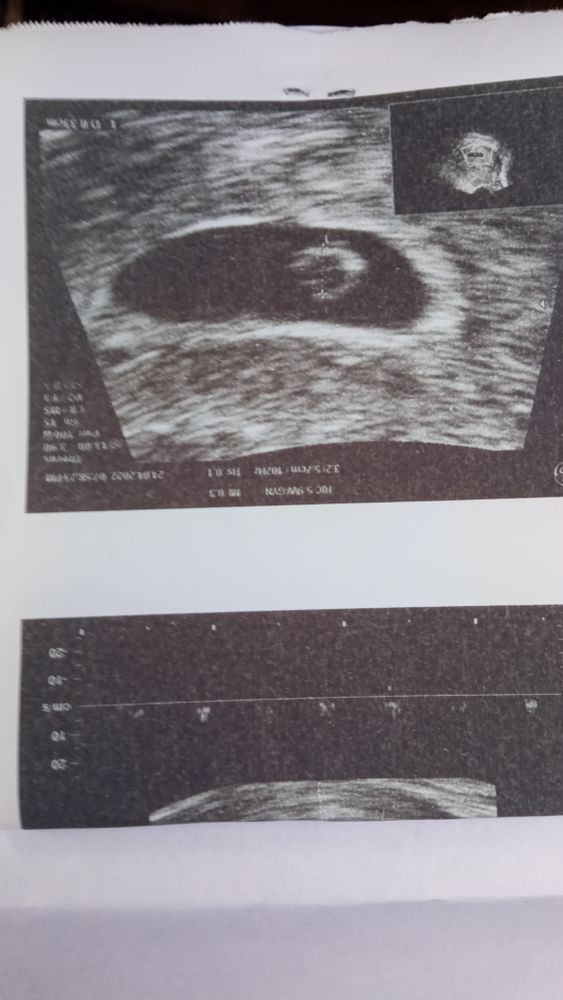

Девчули как у вас дела? У кого получилось забеременеть? В общем я сегодня сходила на УЗИ и вот моя бусинка